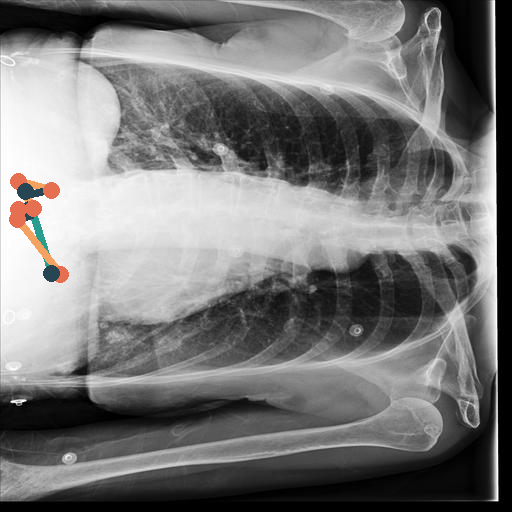

In Fig. 4, we show qualitative examples of the calculation of the SCD for patients for the presence and absence of scoliosis. We can see that the vertebrae segmentation presents a noticeable curvature for the scoliosis case, leading to an SCD above 19, while for the patient with a healthy spine, the SCD is 1.125.

When conducting a t-test, we get a value of 35.30 (p-value 0.0001), indicating a statistically significant difference in SCD between positive and negative patients for scoliosis. On the left of Fig. 4, we show the distributions of the SCD in the form of violin plots for sex, age group, and pathology. Similarly to the CTR, SCD increases with age for the presence and absence of scoliosis. The results show that the older the patient gets, the less the disparity in mean SCD between scoliosis and no scoliosis becomes, indicating that the SCD becomes slightly less insightful the older the patient is. However, different from the CTR, the standard deviation of the SCD is considerably higher, and there is a relatively larger difference in means, leading to a higher predictive value for the identification of scoliosis.

On the right of Fig. 4, we show the ROC-Curve for pathology classification based on the SCD score. We see a difference in the diagnostic performance of the SCD for female and male patients with an AuROC of 0.77 and 0.80.